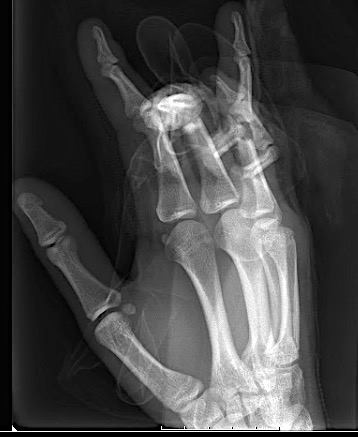

Case 1:

A 64-year-old male suffered a multi-fragmentary fracture of his right thumb metacarpal (Fig 1). An adapted 12-hole strut plate from the variable angle locking hand system was the implant of choice for fixation (Figs 2 - 4).

The strut plate provided good stability in a comminuted extraaricular fracture pattern and enables immediate mobilization. Bone callus formation was not witnessed during the healing process.